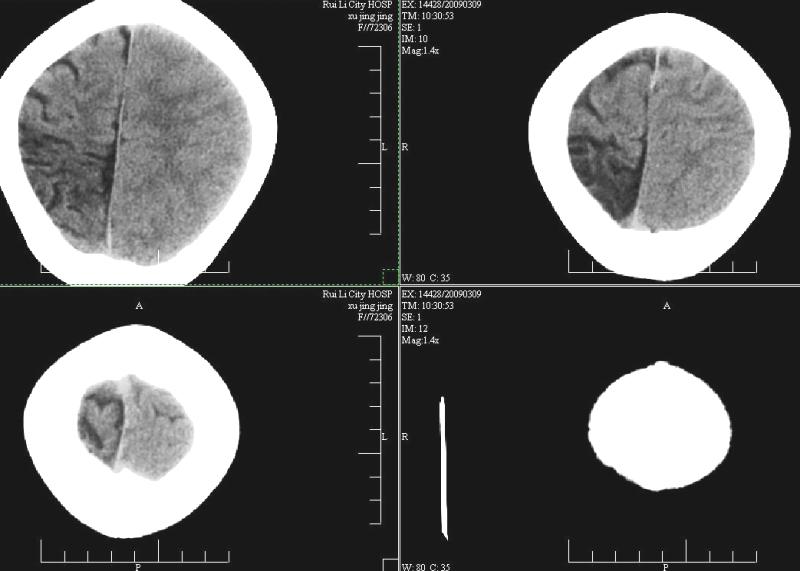

标题: PED1810:F,9岁。头痛,昏倒,一周一次,共半年。 [打印本页]

标题: PED1810:F,9岁。头痛,昏倒,一周一次,共半年。

ct:右顶叶脑软化灶合并右侧大脑半球发育不良可能。

中线平移,象发育不良

支持楼主!右侧强化明显较左侧低.可能血管引起的吧.

支持楼主!右侧强化明显较左侧低.可能由血管发育不良引起的吧.

支持大脑发育不全----右侧大脑中动脉较对侧细小。建议cta 或mra 检查